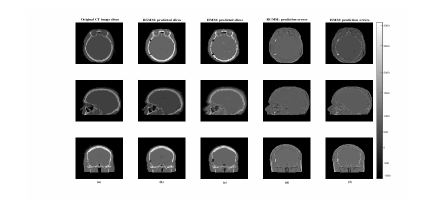

Existing methods have poor performance in the region of the throat cavity [20, 16], and we observed similar behaviour in our method. The results of our approach and HMM are presented in Fig. 10 showing slices of a CT image, its predicted images, and the associated prediction errors, which are conventionally defined as mCTsCT𝑚𝐶𝑇𝑠𝐶𝑇mCT-sCT, for a representative patient.

Refer to caption

Figure 10: The first column (a) represents slices of CT image, the second and third column (b) and (c) shows the corresponding predicted slices of CT images, and the last two columns (d) and (e) show the errors of the prediction.